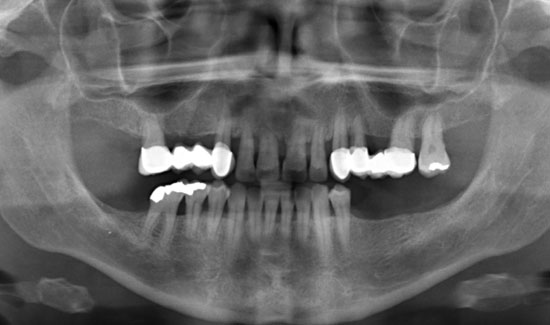

Die Patientin stellte sich in unserer Praxis vor mit der Frage der konservativen Erhaltbarkeit der Oberkieferfrontzähne bei chronischer Parodontitis. Wir fanden generalisierte Taschenbildungen (> 10 mm), Spontanblutungen und einen Lockerungsgrad 2/3, d.h. extraktionswürdige Zähne. Als Überbrückungsmaßnahme (Feiertagssituation) bis zu Sanierungsmaßnahmen boten wir ihr lokale Ozongasbehandlungen an.

Als Ozongasspender verwendeten wir Prozone, das mit Hilfe von Kunststoffansätzen Ozongas schmerzarm in die Taschen einzuleiten erlaubt. Die lokale Ozongas-applikation wurde dreimal im Wochenabstand wiederholt. Außerdem wurde die Patientin auf notwendige persönliche Hygienemaßnahmen aufmerksam gemacht. Wir konnten nicht nur die Blutungen stoppen, sondern den Lockerungs-grad der Zähne in einem stabilen Zustand (2) halten und die messbare Taschentiefe verringern.

Abb. 1: Orthopantomogramm